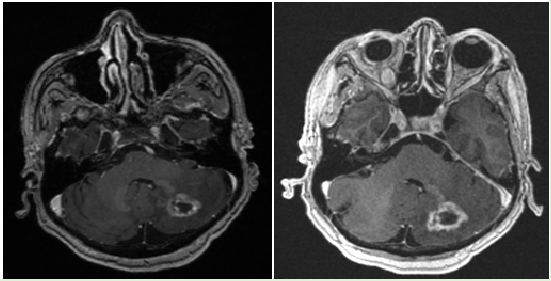

After 2 cycles of therapy with tDM1 a MRI of the brain showed a white matter size increase in the left cerebellum with two new metastasis present on the roof of the fourth ventricle and in the left middle frontal gyrus without mass effect (Figure 1). A craniotomy of the left cerebellum was performed to resect the mass. Pathologist noted that the mass measured 2.3 x 1.7 x 1.5cm. It was cerebriform with a variegated appearance ranging in color from pink to maroon to yellow. Microscopic examination of the specimen displayed coagulated necrosis along with rarified cerebellar white and grey matter. Gliosis, macrophage infiltration, Purkinji cell depopulation, and Bergman gliosis were present. A few esoniophilic granular bodies were also seen. There was no underlying neoplasm, either metastasis, glioma, or hemagioblastoma, present in sample. It was concluded that the presumed metastatic lesion on the left cerebellar was chronic, non-neoplastic and histopathically consistent with radio necrosis, both with the histopathology review and medical records (Figure 2). Patient continued on therapy with tDM1 for almost 1year when she had progression of her cancer in the lungs and breast at which time she was started on pertuzumab, trastuzumab and liposomal paclitaxel. 3months later she had progression of disease and worsening of her performance status so hospice was recommended and she passed away 11months later having lived for more than 6years from her initial diagnosis of metastatic breast cancer.

Figure 1 Axial 3D IR fast SPGR post-contrast images show interval increase in size in a metastatic lesion in the left cerebellar white matter from 1.3 cm x 1.7 cm x 1.7 cm (SAT) (Figure 1a) to 1.6 cm x 1.8 cm x 2.3 cm (SAT) 3 months later (Figure 1b).